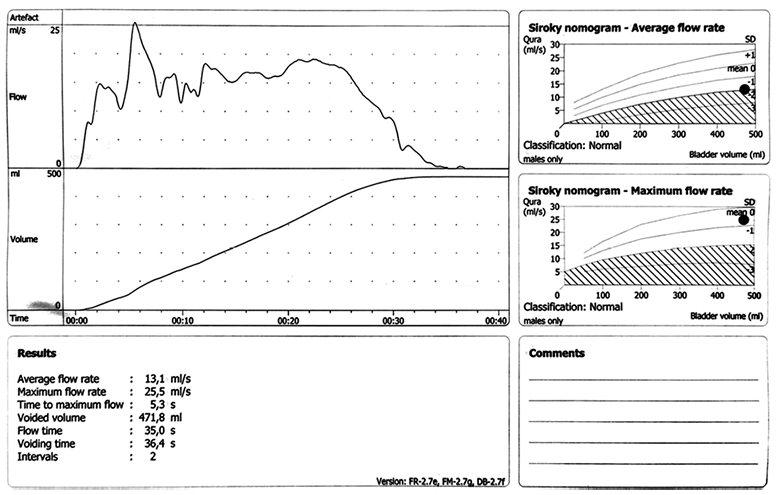

Pacientas patikrintas po 6 mėn. – jis gerai sulaiko šlapimą, įklotų jau nebereikia, šlapinasi normaliai. Atlikus urofloumetrogramos tyrimą (6 pav.), Qmax = 25,5 ml/s.

6 pav. Urofloumetrograma, implantavus antrąjį raištį